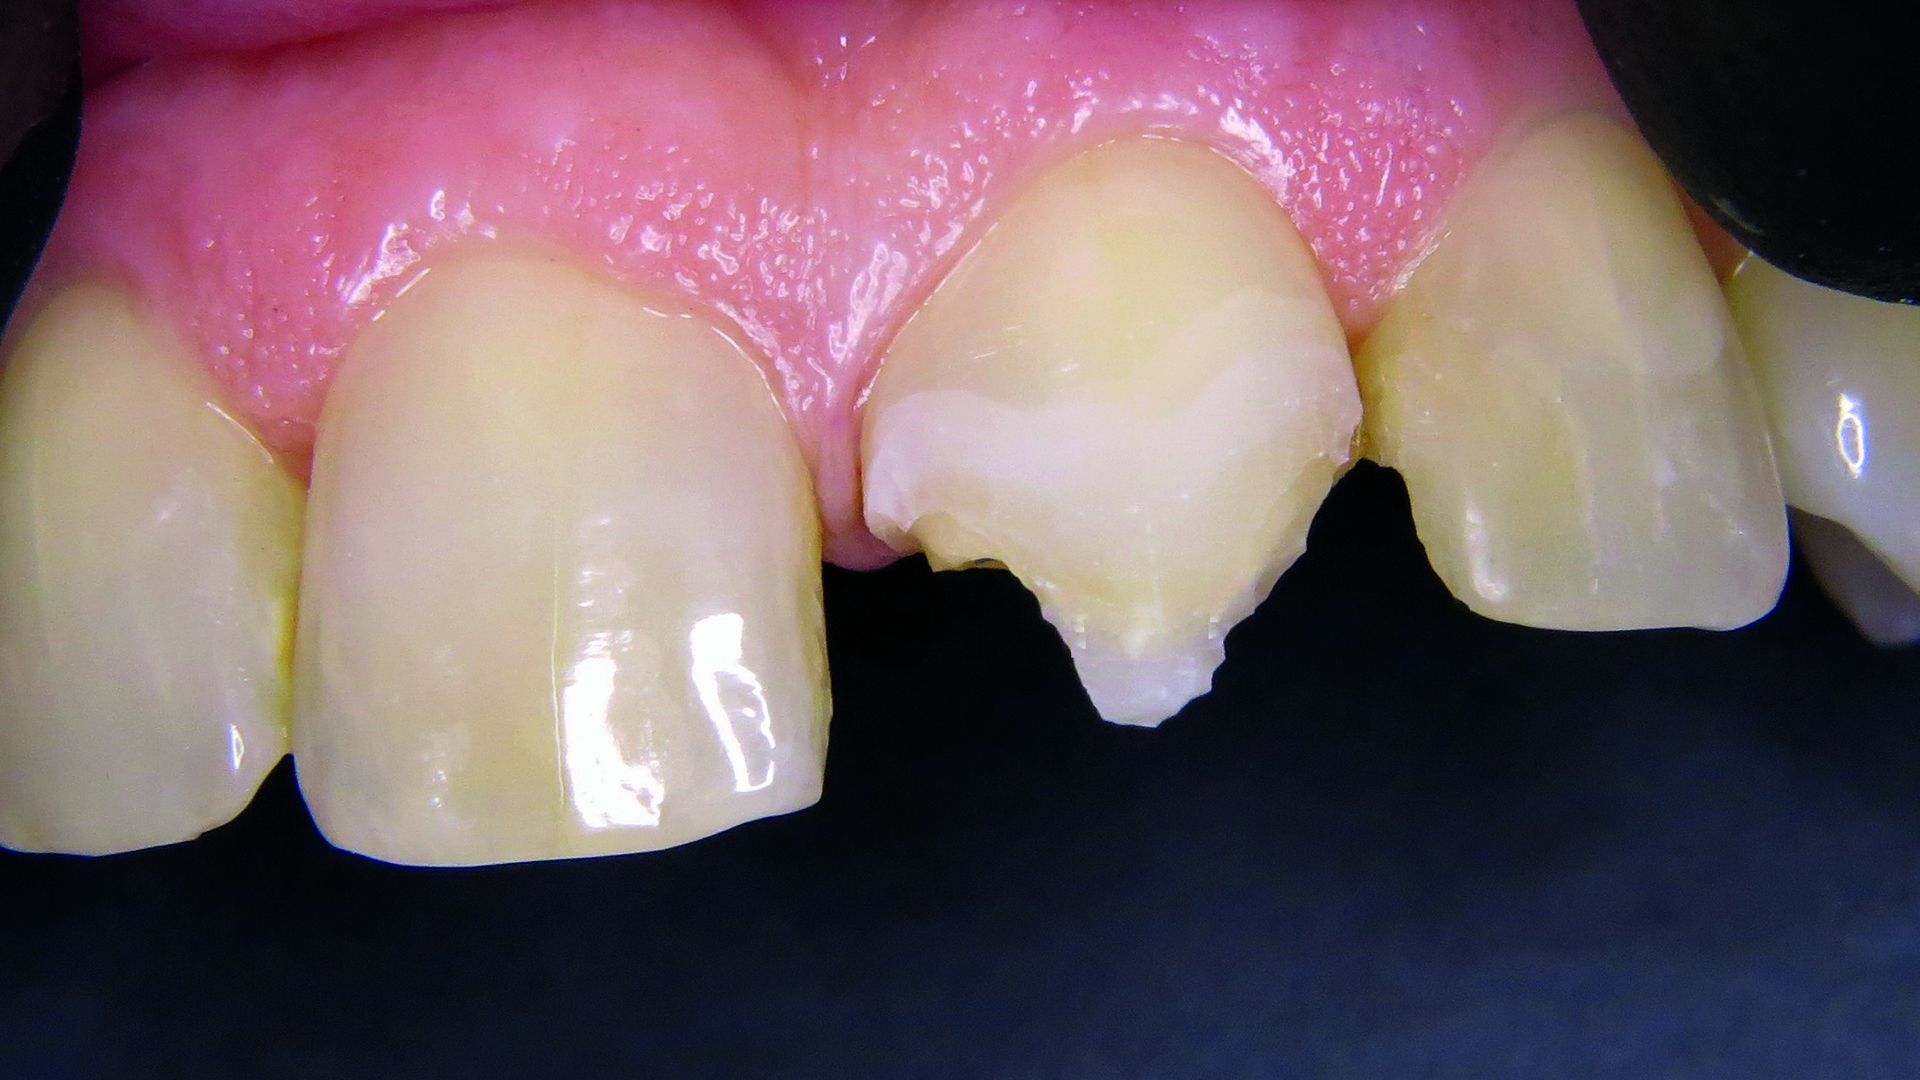

48-letnia pacjentka cierpiąca na alergię wywoływaną przez wiele czynników oraz z historią ataków padaczki w wywiadzie zgłosiła się z życzeniem szybkiego zaplanowania i wykonania estetycznej odbudowy zęba 21, leczonego 10 lat wcześniej (ryc. 1). Zaproponowano pacjentce wykonane analogowo lub cyfrowo uzupełnienie protetyczne lub odbudowę z wykorzystaniem kompozytu opartego na technologii ORMOCER®. Uwzględniając choroby towarzyszące, zdecydowano się zastosować izolację względną. Właściwym dla pacjentki rozwiązaniem okazała się bezpośrednia odbudowa zachowawcza z wykorzystaniem Admira Fusion 5 (VOCO GmbH, Niemcy), gdyż preparat ten nie zawiera klasycznych monomerów. Oczekiwania pacjentki dotyczące estetycznej odbudowy w jak najkrótszym czasie mogły zostać spełnione dzięki wzmocnionemu efektowi kameleona.

Ryc. 1. Pierwotna sytuacja kliniczna – wadliwa rekonstrukcja.

W aspekcie klinicznym stwierdzono w zębie 21 wadliwe wypełnienie z przebarwieniem brzegów i szczeliną brzeżną. Ząb charakteryzował się I stopniem ruchomości, nie był wrażliwy na opukiwanie i nie wykazywał zmian w przyzębiu.